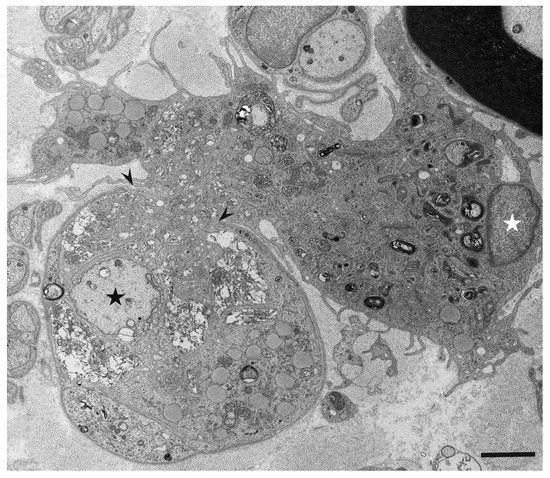

Macrophages and Autoantibodies in Demyelinating Diseases

Myelin phagocytosis by macrophages has been an essential feature of demyelinating diseases in the central and peripheral nervous systems, including Guillain–Barré syndrome (GBS), chronic inflammatory demyelinating polyneuropathy (CIDP), and multiple sclerosis (MS). The discovery of autoantibodies, including anti-ganglioside GM1 antibodies in the axonal [...] Read more.

Myelin phagocytosis by macrophages has been an essential feature of demyelinating diseases in the central and peripheral nervous systems, including Guillain–Barré syndrome (GBS), chronic inflammatory demyelinating polyneuropathy (CIDP), and multiple sclerosis (MS). The discovery of autoantibodies, including anti-ganglioside GM1 antibodies in the axonal form of GBS, anti-neurofascin 155 and anti-contactin 1 antibodies in typical and distal forms of CIDP, and anti-aquaporin 4 antibodies in neuromyelitis optica, contributed to the understanding of the disease process in a subpopulation of patients conventionally diagnosed with demyelinating diseases. However, patients with these antibodies are now considered to have independent disease entities, including acute motor axonal neuropathy, nodopathy or paranodopathy, and neuromyelitis optica spectrum disorder, because primary lesions in these diseases are distinct from those in conventional demyelinating diseases. Therefore, the mechanisms underlying demyelination caused by macrophages remain unclear. Electron microscopy studies revealed that macrophages destroy myelin as if they are the principal players in the demyelination process. Recent studies suggest that macrophages seem to select specific sites of myelinated fibers, including the nodes of Ranvier, paranodes, and internodes, for the initiation of demyelination in individual cases, indicating that specific components localized to these sites play an important role in the behavior of macrophages that initiate myelin phagocytosis. Along with the search for autoantibodies, the ultrastructural characterization of myelin phagocytosis by macrophages is a crucial step in understanding the pathophysiology of demyelinating diseases and for the future development of targeted therapies. Full article